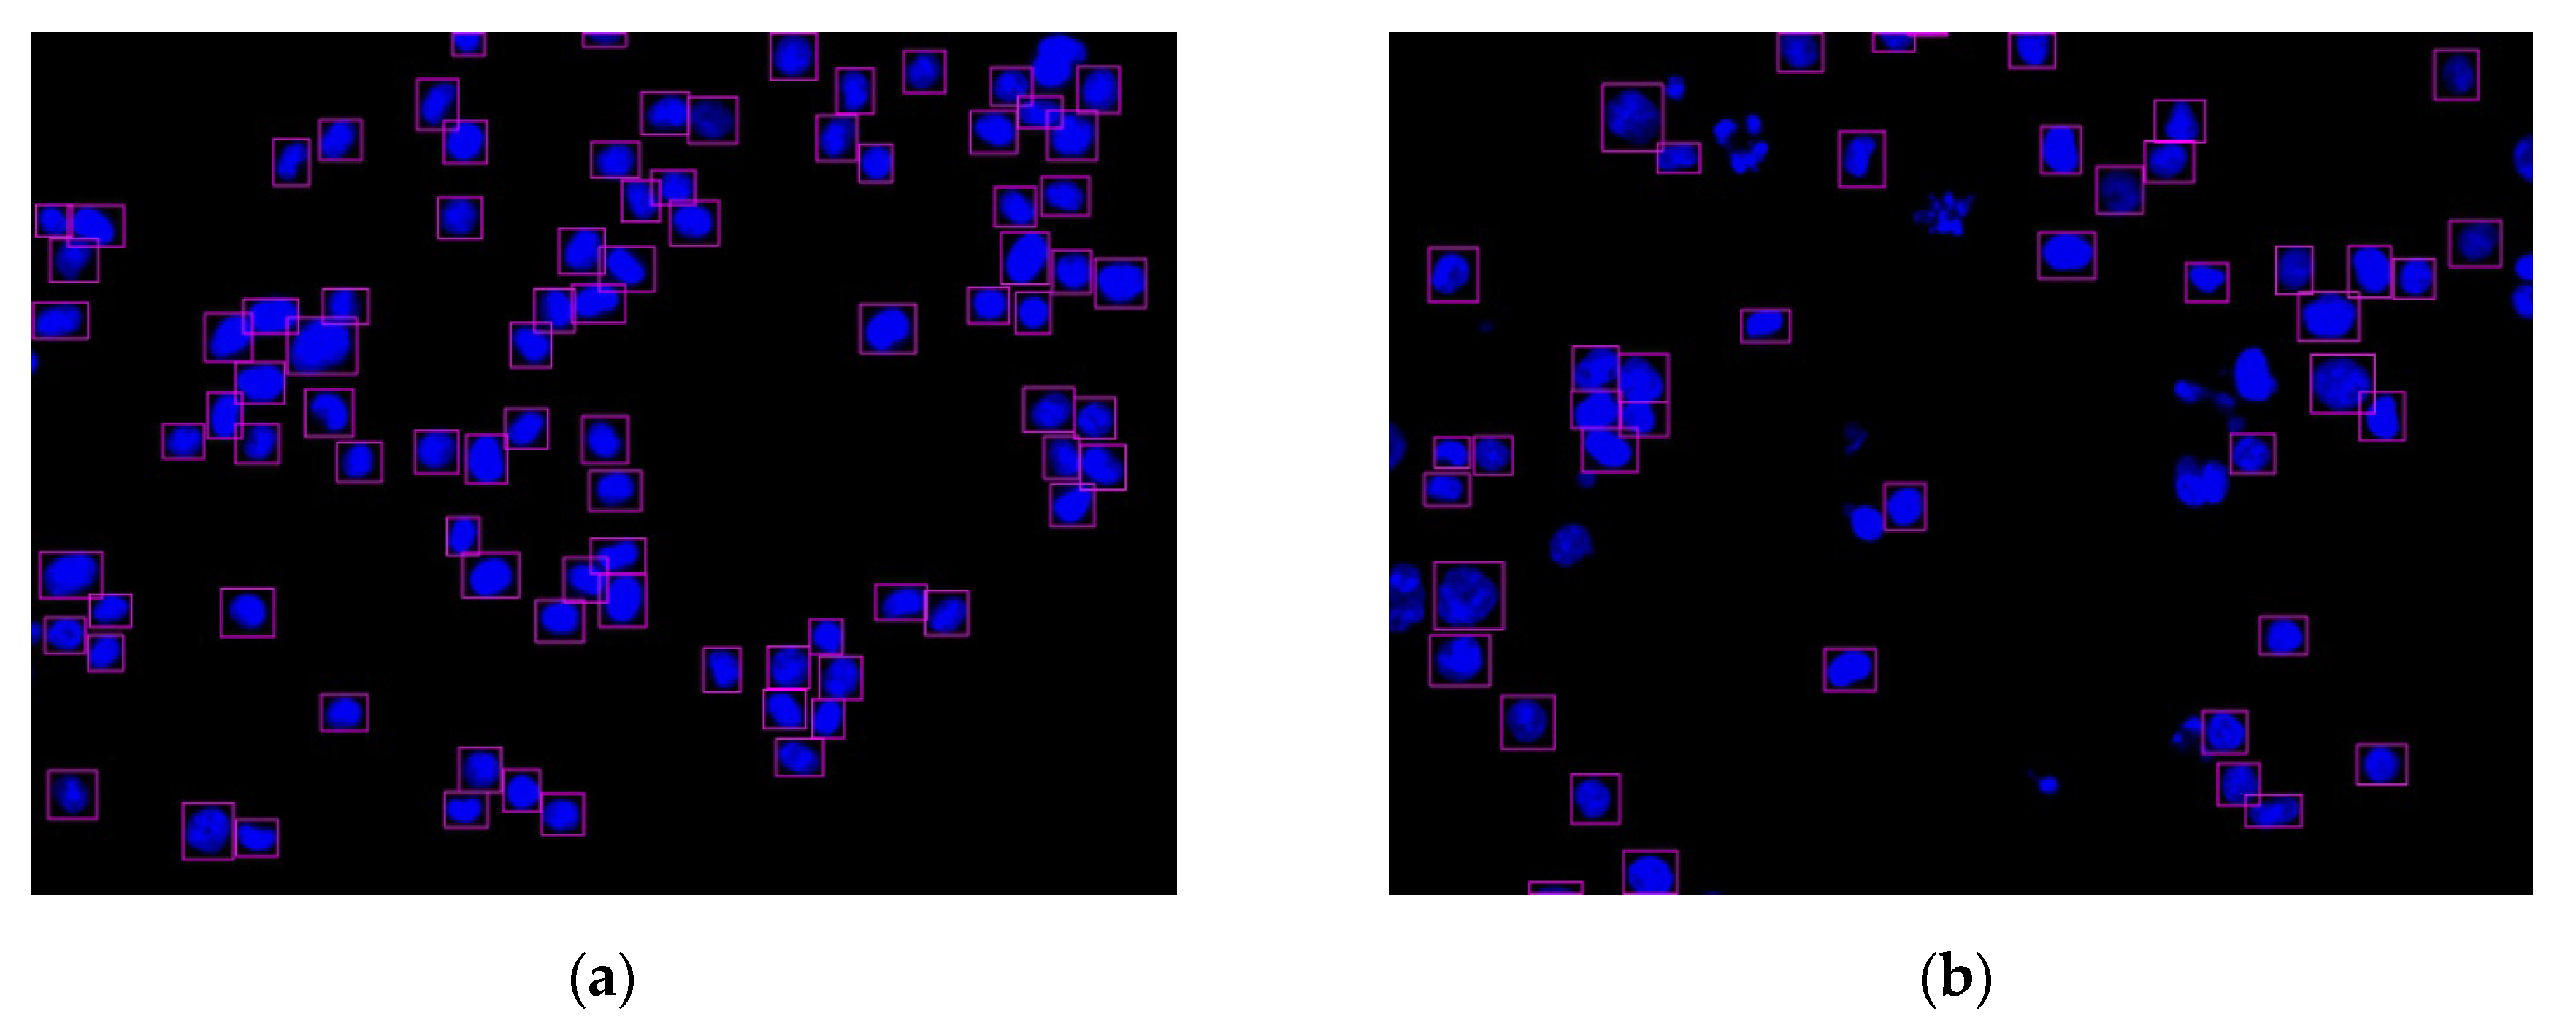

Figure 12.

Two nucleus images recognized by the YOLO algorithm: (a) HCT116 cell with DMSO (no.4484); (b) HCT116 cell with dinaciclib (no.4496).

Figure 13 shows the function of each step in this experiment. The images of the cell nuclei and cytoskeleton are shown in Figure 13, which is separated from Figure 9. We used k-means clustering [38] for the color quantization of blue elements in the images (the number of quantized colors, k = 15). The background was then removed to obtain the cell nucleus regions, and the lowest quantized color grayscale value was used as the background color. The regions with values higher than the background color are considered to be the cell nucleus and cytoskeleton regions. Figure 13 shows the results: Figure 13a1–a4 show the images after color quantization, while Figure 13b1–b4 show the cell nucleus and cytoskeleton regions after the background is removed. We used the cytoskeleton region (N) to obtain the valid cell nucleus regions (N∩C), and the results are shown in Figure 14. After the P (=N−B−D) operation, no valid regions were present in Figure 14a (the four regions are located at the edges of the image). However, Figure 14b contains 10 invalid regions, and 12 regions are located at the edges of the image (rectangular box with diagonal lines).

Figure 14.

Invalid nucleus regions and regions in boundary detection by P (=N-B-D) operation (rectangular box with diagonal lines): (a) HCT116 cell with DMSO (no.4484); (b) HCT116 cell with dinaciclib (no.4496).